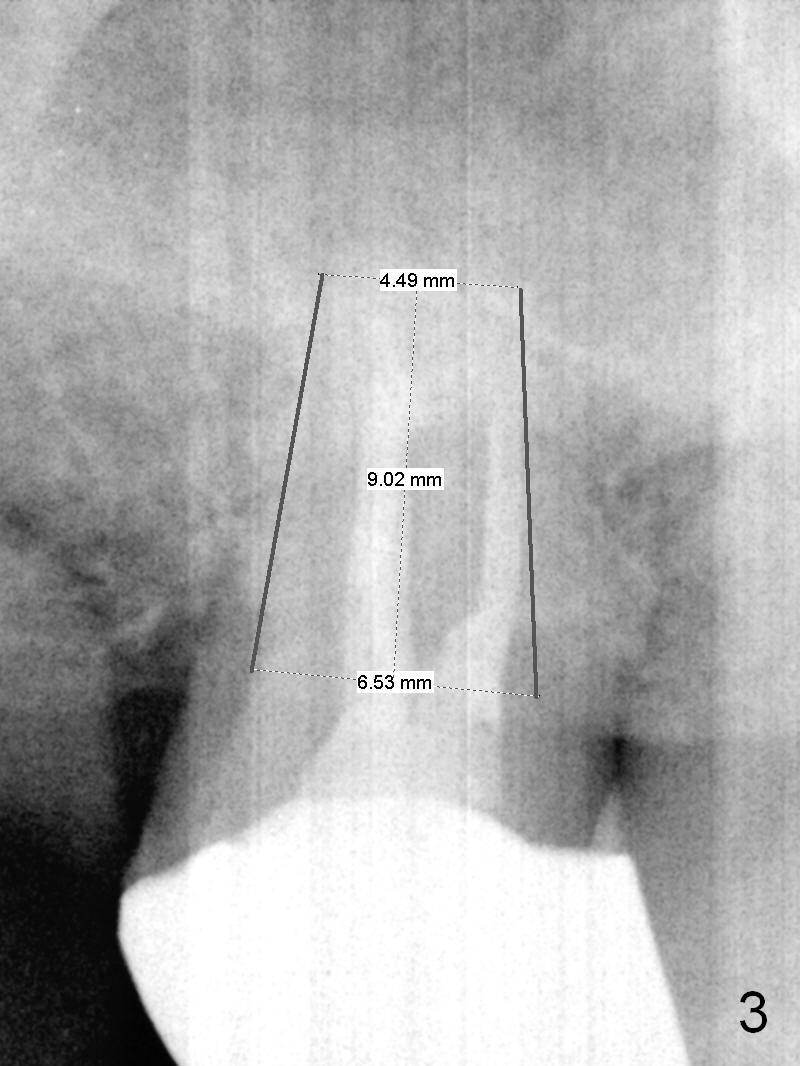

A 52-year-old man has had mild cold sensitivity for the last 3 years since RCT was done at the tooth #2 (3 canals, MB2 not found, Fig.1 (preop), 2 (taken today, pain more severe)). After discussion of treatment options (including RCT retreat), the patient chooses extraction and implant. The planned implant is 6.5x9 mm (Fig.3). As expected, the 3 roots are fused (Fig.4). The socket is single and triangular (Fig.6 green outline (black one: gingival margin)). What is not really expected is the presence of the possible MB2 canal (Fig.5 *). The mesiodistal width of the buccal roots and palatal one are 6.5 and 4.5 mm, respectively. The diameter of the planned immediate implant is estimated to be 5 mm. The socket depth is 11 and 13 mm to the crest and the gingiva, respectively. After use of Magic Expanders (ME) from 3.0-4.3 mm for sinus lift, a 5x11 mm dummy implant is placed. The implant (Fig.7 red circle) has 3 pointed contact so it is stable, but it is placed apically (Fig.8). After removal of the dummy implant, allograft is placed (.5-1.5 mm) before insertion of a 5.5x11 mm implant with satisfactory stability (Fig.9). Postop, the patient reports light bloody nasal discharge with bone graft. Ideally with the narrow mesiodistal socket, it is unnecessary to penetrate the sinus floor with ME. A 5x9 mm dummy implant should have been placed with well-controlled implant placement depth. It is followed by inserting an implant .5 mm larger for the maxilla. IBS implants are easy to achieve primary stability. Insertion torque of 20 Ncm is sufficient to load abutment (5x4(4) mm) and immediate nonfunctional provisional.